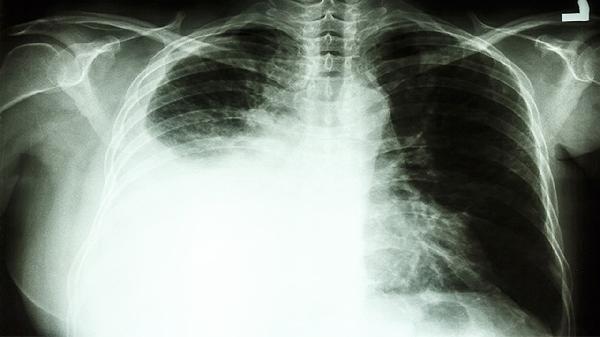

外照射治疗通过直线加速器等设备从体外定向照射肿瘤区域。该方法适用于乳腺癌、肺癌等实体肿瘤,治疗过程中需要精确定位病灶位置,通常分多次进行以保护正常组织。常见副作用包括照射部位皮肤反应、乏力等,现代调强放射治疗技术能显著降低周围器官损伤。